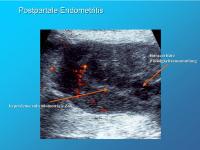

Postpartale Endometritis

Abbildung 11

Keywords: CavumechoEndometritisFarbdopplerWochenbett